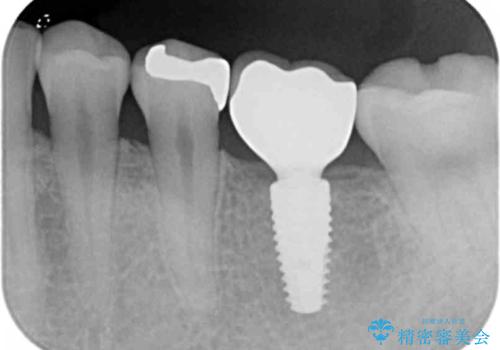

抜歯後、骨の再生を待ったことで、清掃性の高い位置に埋入を行い機能的・審美的なインプラント治療を行うことができました。